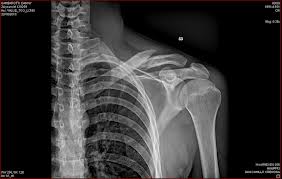

Queste lesioni cutanee erano associate a strie cutanee e a lesioni ossee, rilevate nel corso di un esame radiografico These skin lesions were associated with skin striae and bone lesions first seen during an Xray examination. Se si sospettano metastasi ossee per il reperto occasionale di lesioni litiche multiple, la ricerca del tumore primitivo può iniziare con la valutazione clinica per le principali forme neoplastiche (in particolare va focalizzata sul seno, la prostata e la tiroide), con una RX torace, una mammografia e la misurazione dei livelli di Ag prostatico specifico. Ha gravi lesioni ossee Er hat zahlreiche Knochenbrüche Due protrusioni ossee tra i lobi parietali e quello occipitale Sie werden Missbildungen an der Wirbelsäule finden und zwei knöcherne Auswüchse zwischen Hinterhaupt und Scheitelbein.

La radiografia è il primo esame che consente di osservare lesioni ossee grossolane o un anomalo aspetto dell’osso con possibili calcificazioni puntiformi o una tarlatura nella trabecolatura dell’osso stesso (tipo un forellino) o un’escrescenza ossea Ad un occhio esperto già da una semplice radiografia è possibile fare diagnosi di. Metastasi ossee da CaP • L’apparato scheletrico è la sede preferenziale delle metastasi da CaP • La maggioranza delle lesioni ossee è di tipo osteoblastico • In studi autoptici la prevalenza del coinvolgimento dell’apparato scheletrico nei pazienti che muoiono per CaP è superiore all’80 %Jacobs, 19 11. Osteoaddensante delle lesioni ossee, dalla loro sede e numero, dalla gestione e dal trattamento delle complicanze stesse Il dolore è il sintomo più frequente (2,3) Gli eventi scheletrici e il dolore hanno dimostrato in diversi studi di peggiorare in maniera.